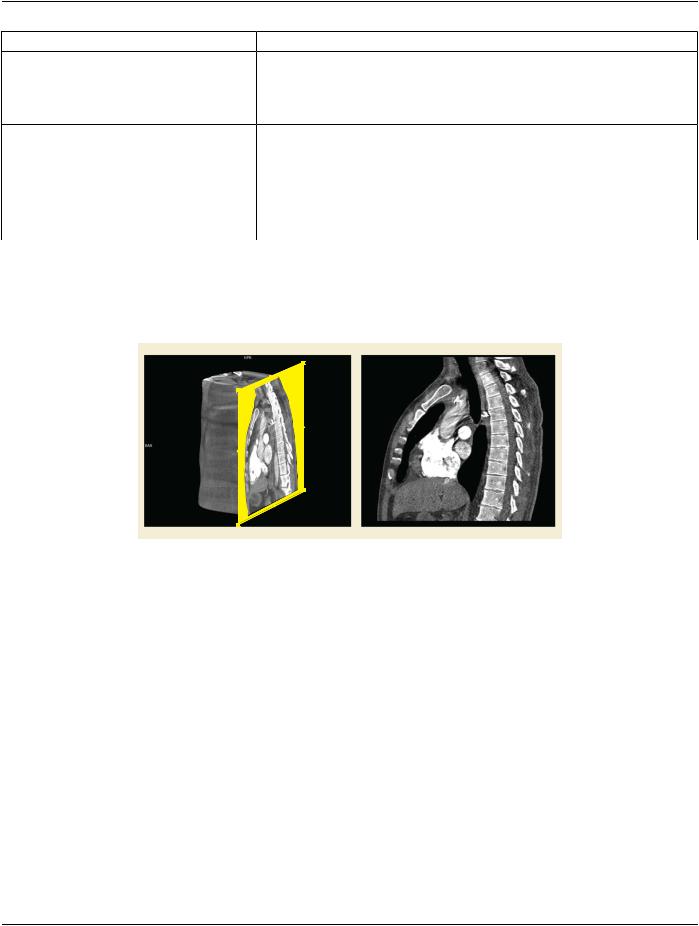

Figure C.11.26-1. Volume Rendering with visualization of MPR plane orientation and resulting PLANAR​ MPR rendering​

A PLANAR MPR is a thin slice or thick slab of the input volume defined by a geometric plane as illustrated by Figure C.11.26-1. Fig-​ ure C.11.26-2 and Figure C.11.26-3 depict the relationships between MPR Geometry Module Attributes and Thin and Slab MPR​ views, respectively.​